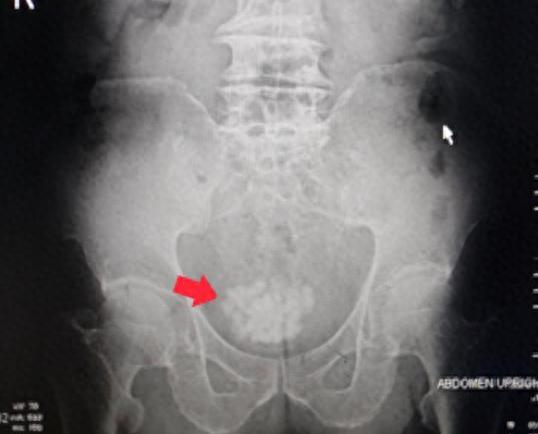

检查结果

(膀胱内大量结石)

检查发现,李爷爷的膀胱里面已经长满了结石,前列腺达到了68x61x54毫米,属于极重度前列腺增生。